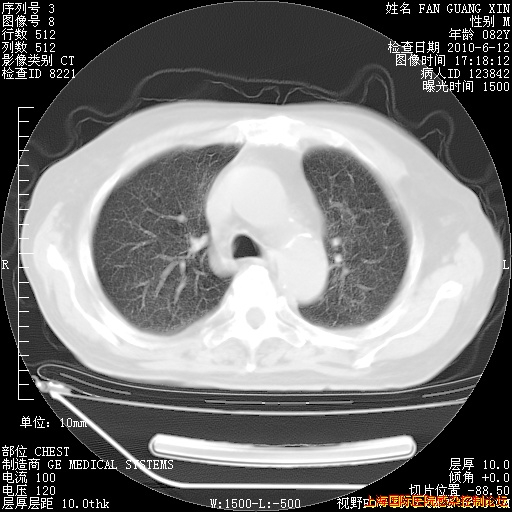

今天复查CT

整整相隔30天的肺部CT好像有所好转啊。甲强龙减量第3天,需要观察体温。